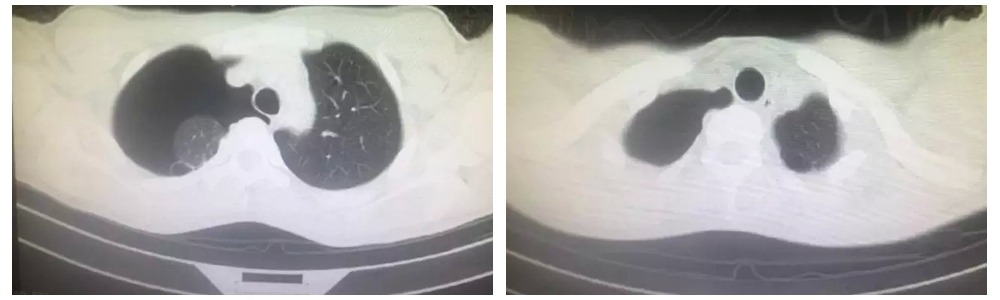

患者周某,是一名高三學(xué)生,因胸痛氣促入院。查胸CT顯示右側(cè)氣胸閉式引流術(shù)后,右肺被壓縮約60%,雙上肺尖多發(fā)肺大皰。經(jīng)詳問病史,患者既往左側(cè)有氣胸發(fā)作史。經(jīng)術(shù)前各項(xiàng)檢查,科室人員積極討論,考慮到患者為在校高三學(xué)生,右肺大泡并氣胸經(jīng)閉式引流術(shù)后肺復(fù)張不良,曾有氣胸發(fā)作史,胸部CT可見雙肺明顯肺大泡,保守治療復(fù)發(fā)率高,甚至出現(xiàn)張力性氣胸危及生命可能,遂決定行經(jīng)劍突下胸腔鏡雙肺肺大皰切除術(shù)。